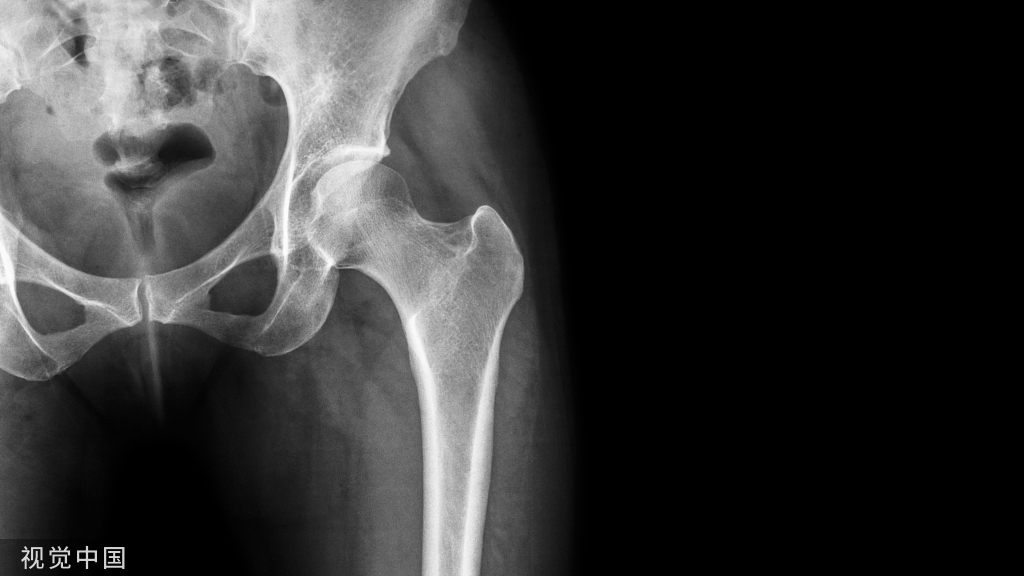

半月板损伤是指半月板受到外力的作用而导致撕裂、破裂,继而出现膝关节周围疼痛、交锁等症状。